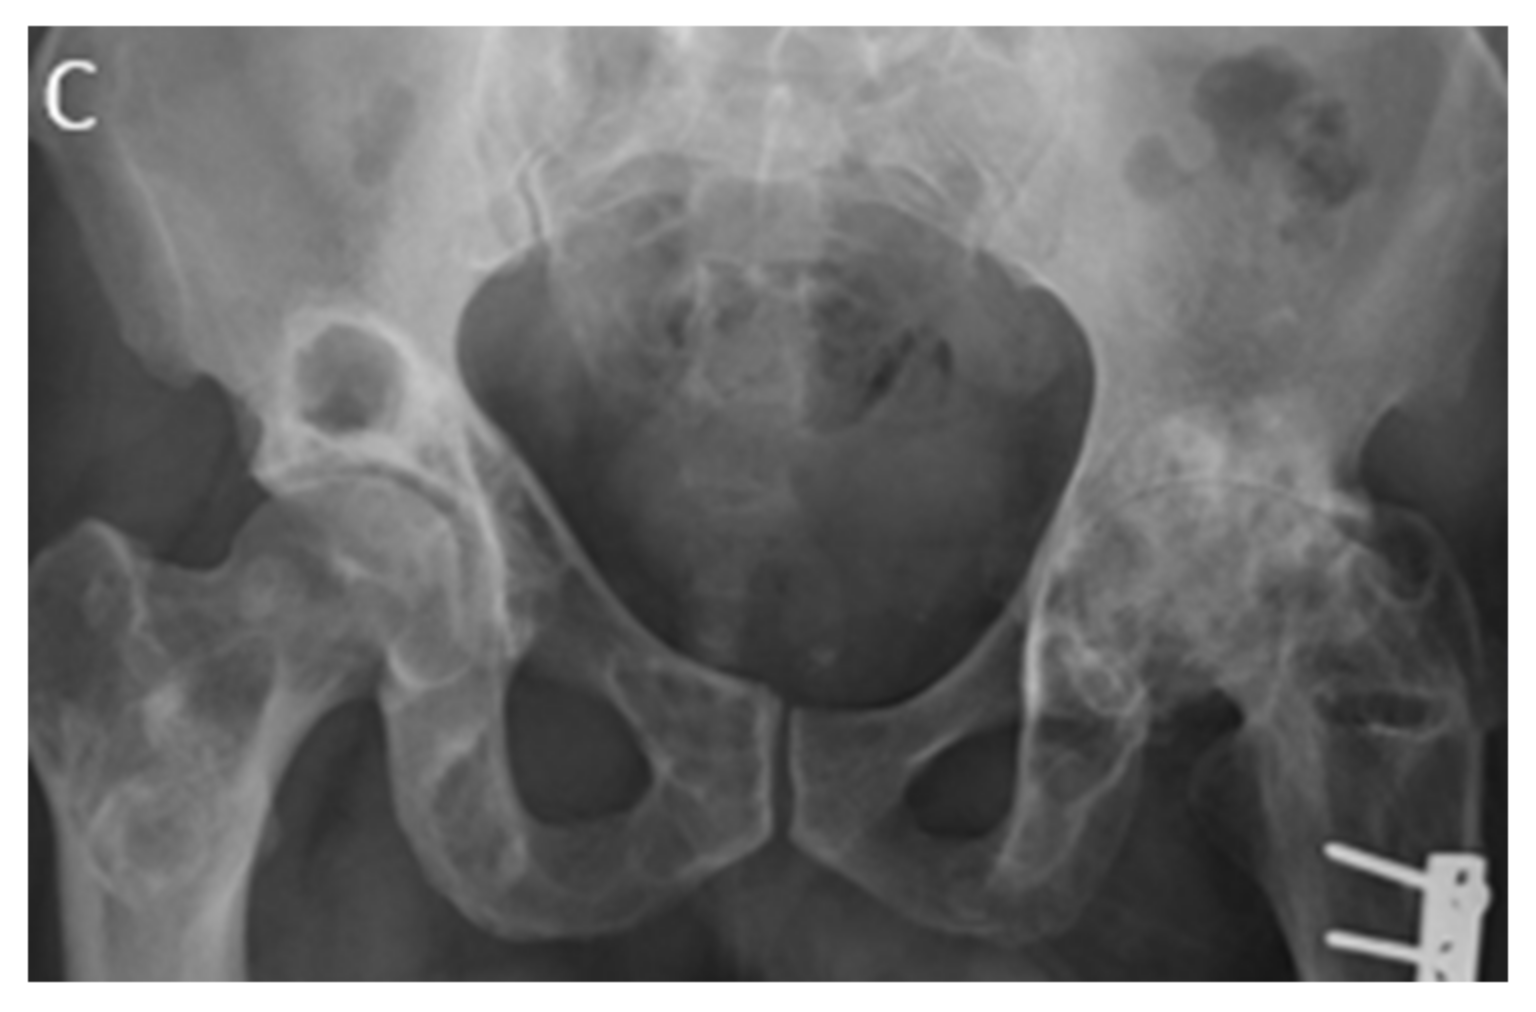

7.7. Paget’s Disease of the Rib

- Theodorou, D.J.; Theodorou, S.J.; Kakitsubata, Y. Imaging of Paget disease of bone and its musculoskeletal complications: Review. AJR Am. J. Roentgenol. 2011, 196 (Suppl. 6), S64–S75. [Google Scholar] [CrossRef]

- Park, E.T.; Kim, S.E. Radiography, Bone Scan, and F-18 FDG PET/CT Imaging Findings in a Patient with Paget’s Disease. Nucl. Med. Mol. Imaging 2010, 44, 87–89. [Google Scholar] [CrossRef][Green Version]

| Paget’s disease of the rib | Osseous expansion, cortical thickening, and trabecular coarsening | Blastic phase: hypointense on both T1W and T2W images Lytic phase: speckled hypointense on T1W and hyperintense on T2W, T1WFS + C enhancement |